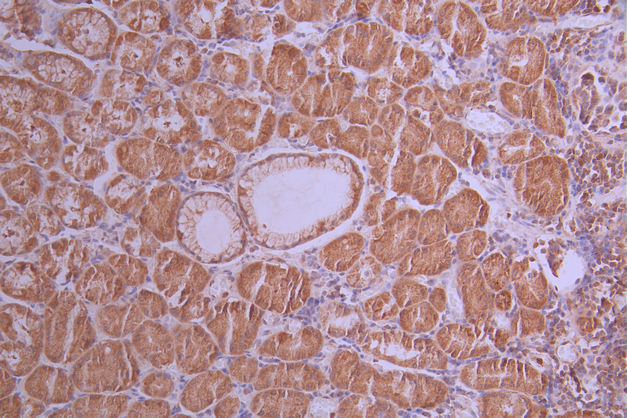

IHC image of CSB-RA297595A0HU diluted at 1:100 and staining in paraffin-embedded human gastric cancer performed on a Leica BondTM system. After dewaxing and hydration, antigen retrieval was mediated by high pressure in a citrate buffer (pH 6.0). Section was blocked with 10% normal goat serum 30min at RT. Then primary antibody (1% BSA) was incubated at 4°C overnight. The primary is detected by a Goat anti-rabbit polymer IgG labeled by HRP and visualized using 0.05% DAB.

IHC image of CSB-RA297595A0HU diluted at 1:100 and staining in paraffin-embedded human testis tissue performed on a Leica BondTM system. After dewaxing and hydration, antigen retrieval was mediated by high pressure in a citrate buffer (pH 6.0). Section was blocked with 10% normal goat serum 30min at RT. Then primary antibody (1% BSA) was incubated at 4°C overnight. The primary is detected by a Goat anti-rabbit polymer IgG labeled by HRP and visualized using 0.05% DAB.